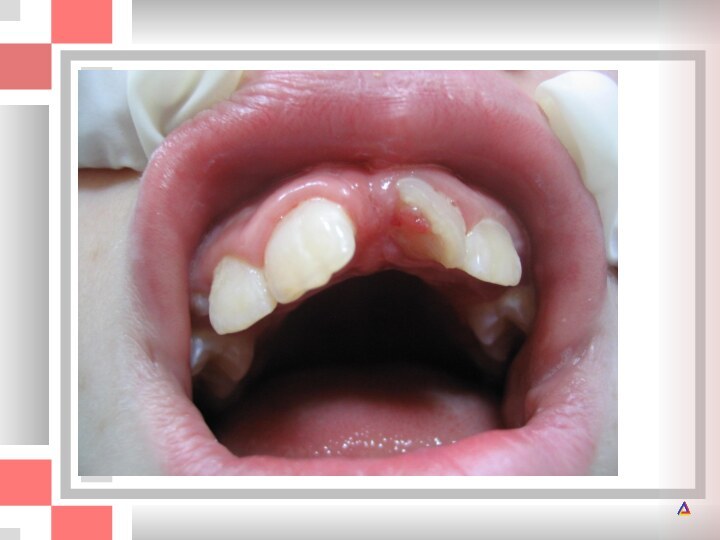

Слайд 17 Год назад левый молочный центральный резец получил травму.

Год назад левый молочный центральный резец получил травму. После травмы зуб

После травмы зуб казался здоровым, однако впоследствии анкилозировался, что

не позволило ему полностью прорезаться.

Анкилоз постоянного центрального резца после травмы. Прорезывание резца прекратилось. Зуб следует удалить.